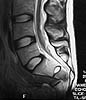

MR1

A 28 year old male jumped from the 4th floor on 11-25-2000 sustaining an L1 burst fracture that has been fixed anteriorly by the neurosurgeon with a strut between T12 and L2. A Kaneda device was placed anteriorly as well. My concern is the pelvic ring injury. There are bilateral sacral fractures through the foramen and a transverse element through the sacrum between S2 and S3. the lower part of the sacrum is displaced forward. Anteriorly there are right superior and inferior pubic rami fractures.

He also has bowel and bladder sxs. The neurologic injury could be from the L1 burst or from the sacrum or both.